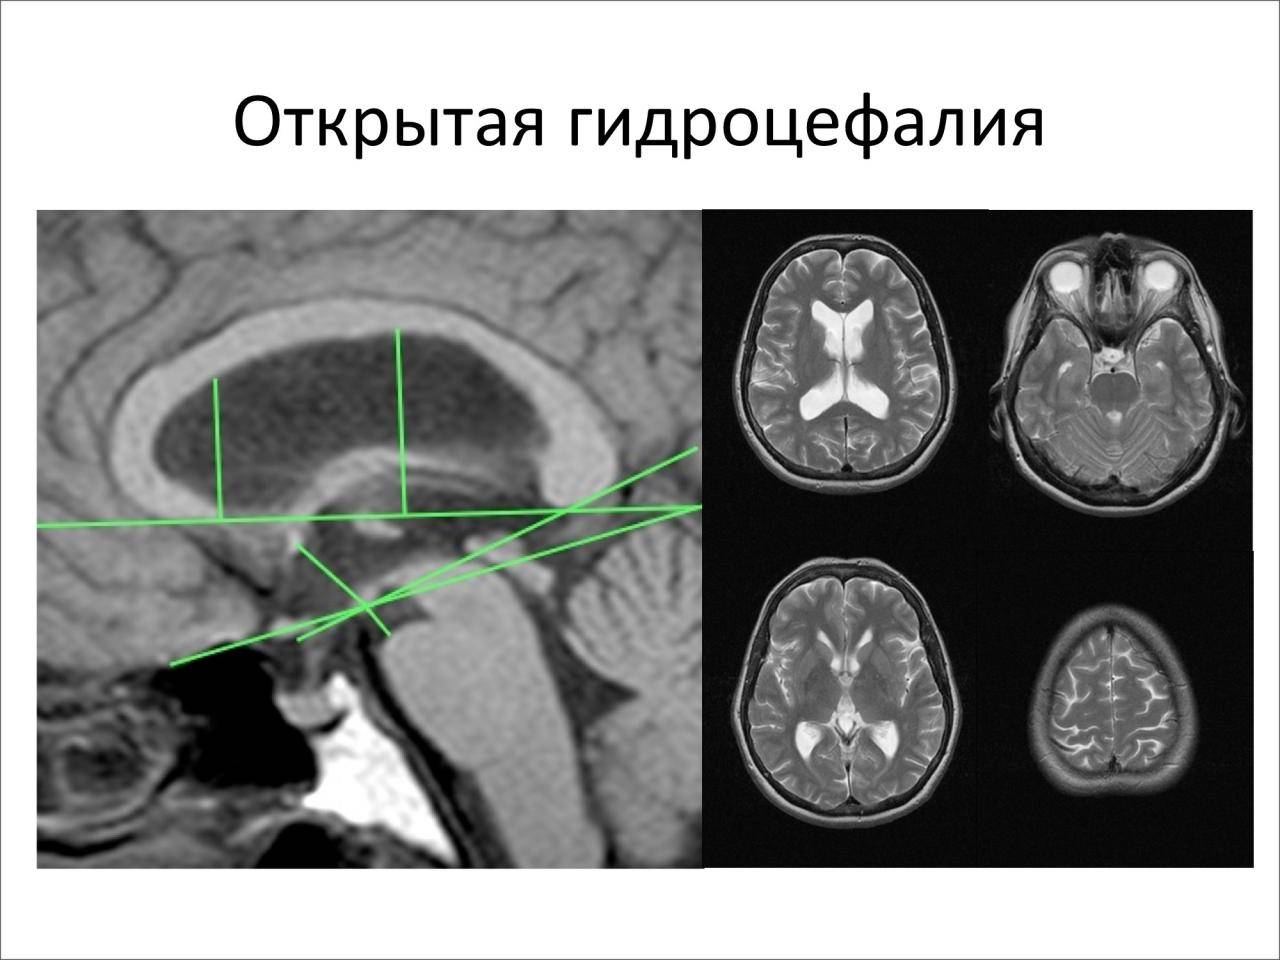

Признаки умеренно выраженной наружная

Признаки умеренно выраженной наружная 113 фото